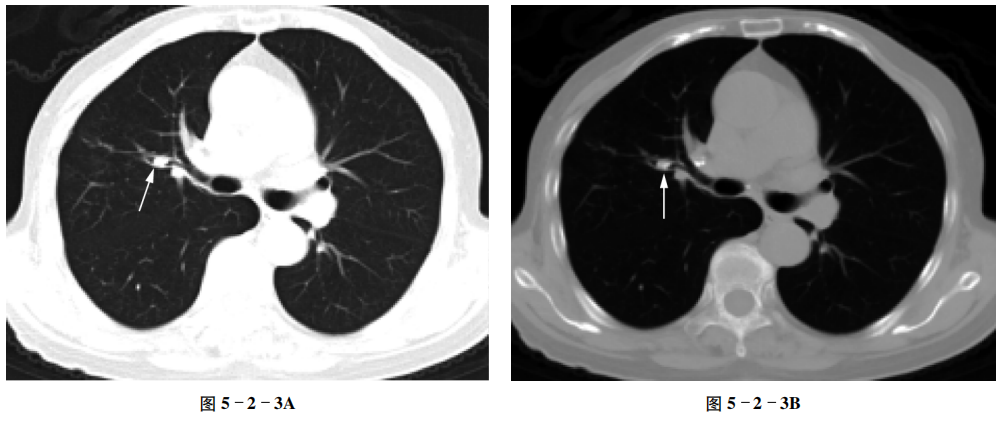

例3 支气管结石

【病史摘要】 女性,75岁。反复咳嗽,有糖尿病病史。

【CT征象】 右肺上叶后段局部支气管稍扩张,其管腔内见结节状钙化密度影(箭头),支气管管腔狭窄。右肺门见淋巴结钙化影(图5-2-3A、B)。

【重要征象】 支气管腔内结节状高密度影,CT值>100 HU。

【CT拟诊】 ① 支气管结石。② 支气管肿瘤。③ 支气管异物。

【病理诊断】 支气管结石。